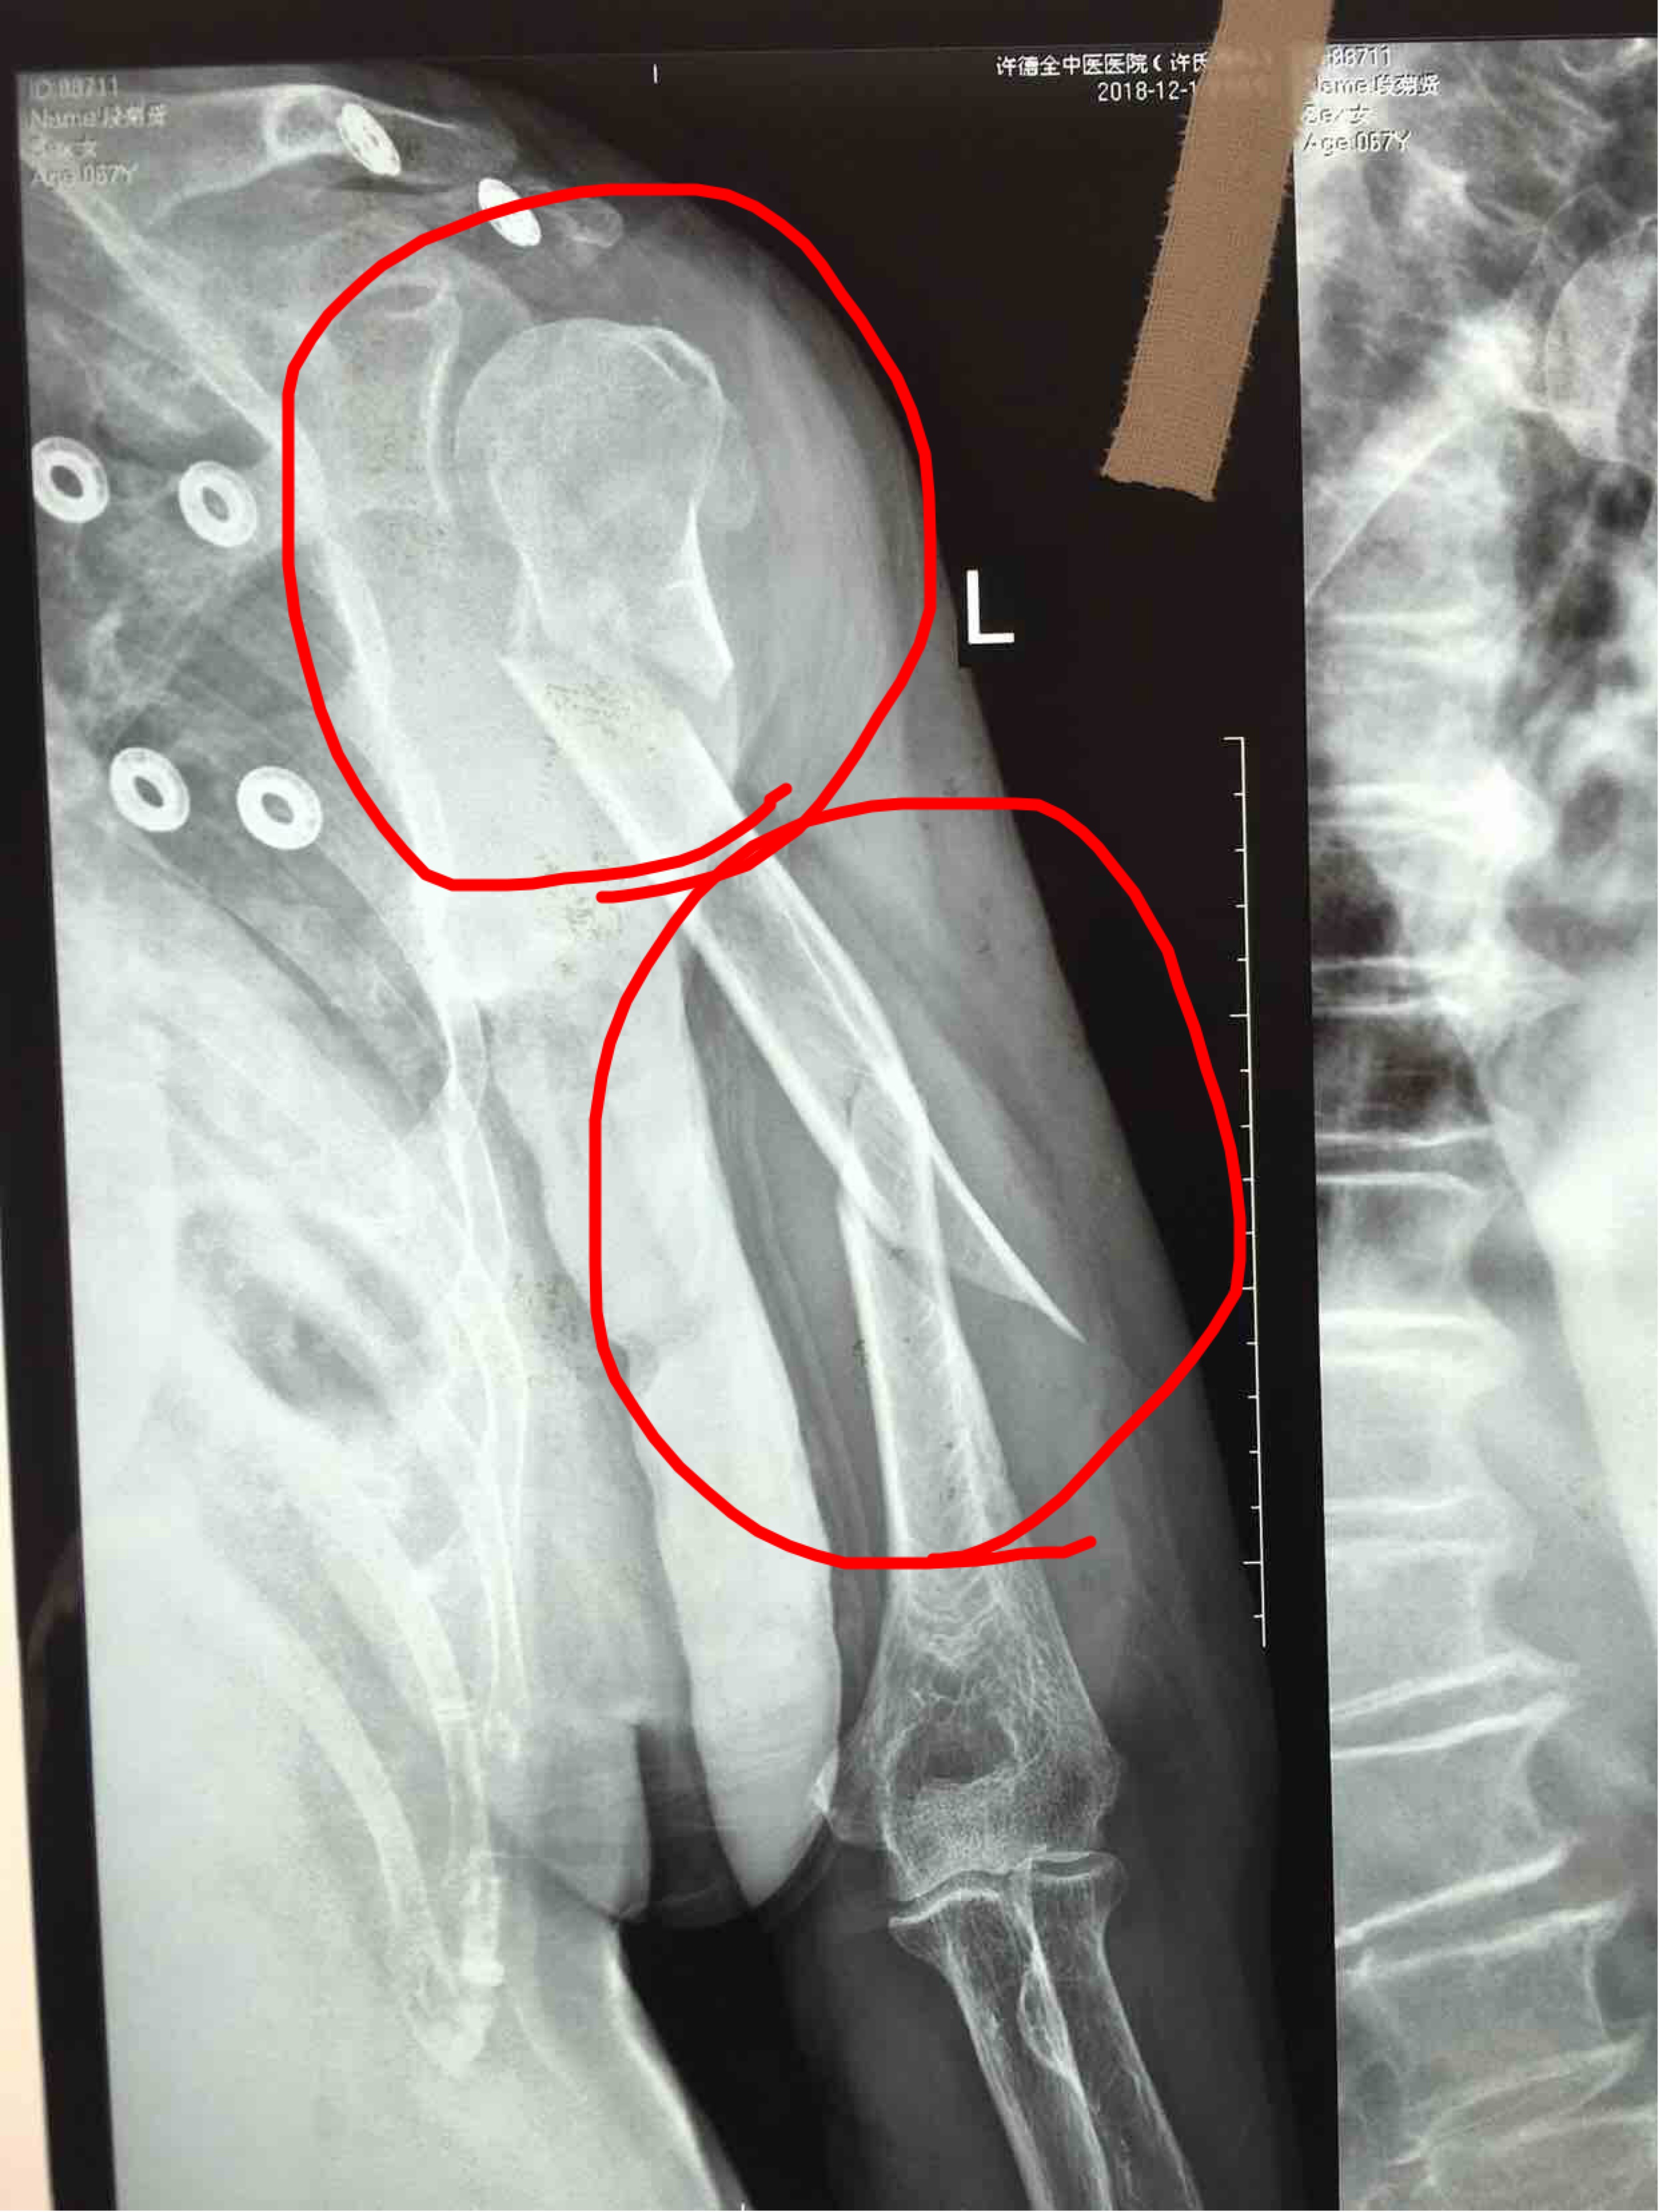

肱骨外科颈粉碎性骨折并肱骨干骨折(切复内固定术)

骨折 肱骨干骨折

摔伤后左上肢肿痛,畸形,活动受限2小时入院。既往身体健康。无特殊不良嗜好。

心肺腹未见异常,生命体征平稳。左上肢肿胀明显,畸形,局部皮色皮温基本正常,压痛及纵叩痛阳性,异常活动,末梢血运感觉正常。

诊断:1.肱骨外科颈粉碎性骨折        2.肱骨干骨折完善术前准备,在臂丛麻醉下行切复内固定术,近端选择解剖型锁定钛板,干部选择普通加压钛板,术中注意充分止血,保护尺神经,固定顺序先外科颈后干部。

术中外科颈粉碎成四部分骨折,只做了立线及颈干交的复位,保证功能复位。还有不足之处望各位老师指正!谢谢!